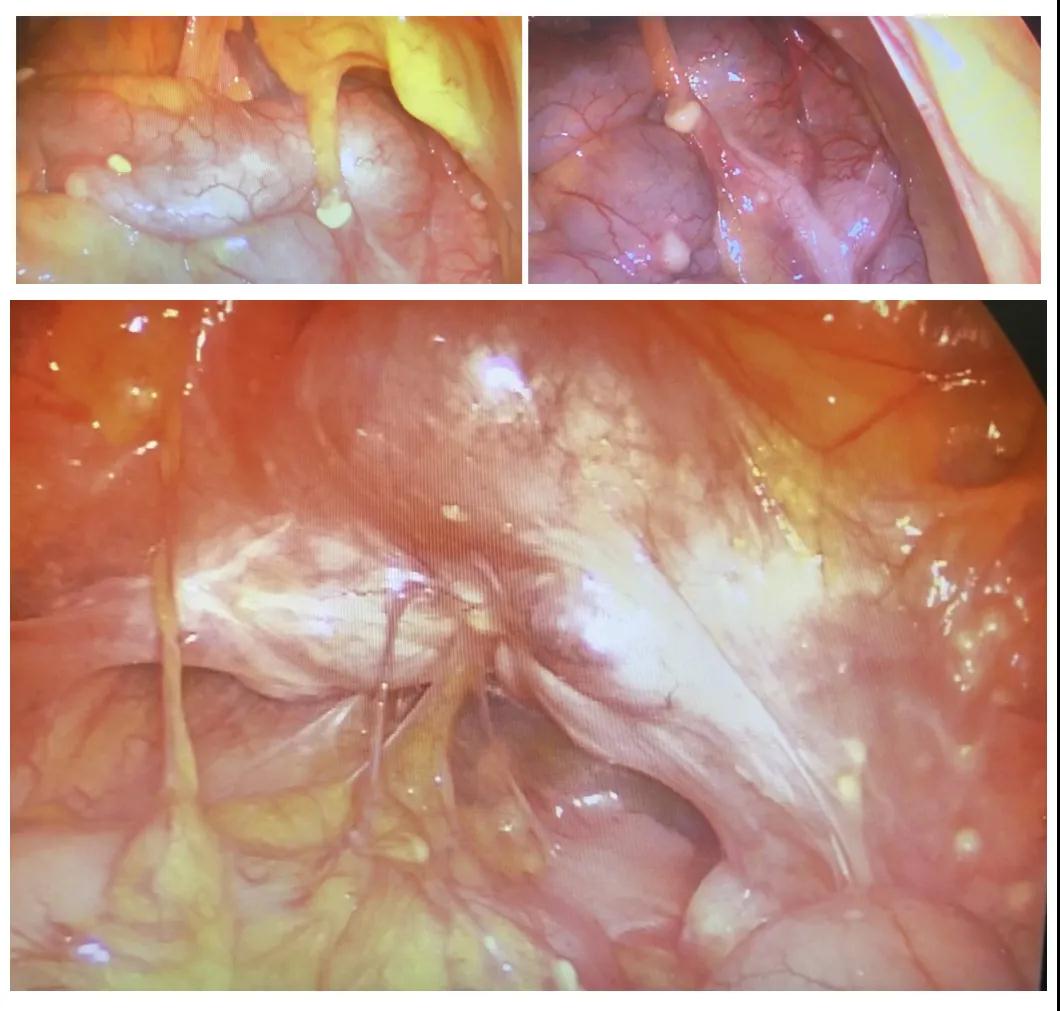

手術(shù)當(dāng)天,通過(guò)腹腔鏡探查發(fā)現(xiàn),小琳腹腔廣泛粘連,分粘后發(fā)現(xiàn)雙側(cè)卵巢有約5cm大小囊腫,且雙側(cè)輸卵管積水、傘端閉鎖,同時(shí)還在小琳的盆腔腹壁、骶前、腸管、腸系膜,發(fā)現(xiàn)了大量散在的大小約0.1cm~0.6cm的灰色結(jié)節(jié),性質(zhì)無(wú)法辨別。

(小琳盆腔部分結(jié)節(jié))

冷院長(zhǎng)遂即同小琳家屬商量,進(jìn)行冰凍切片,結(jié)果為良性病變(附件包塊),盆腔結(jié)節(jié)考慮是盆腔結(jié)核。